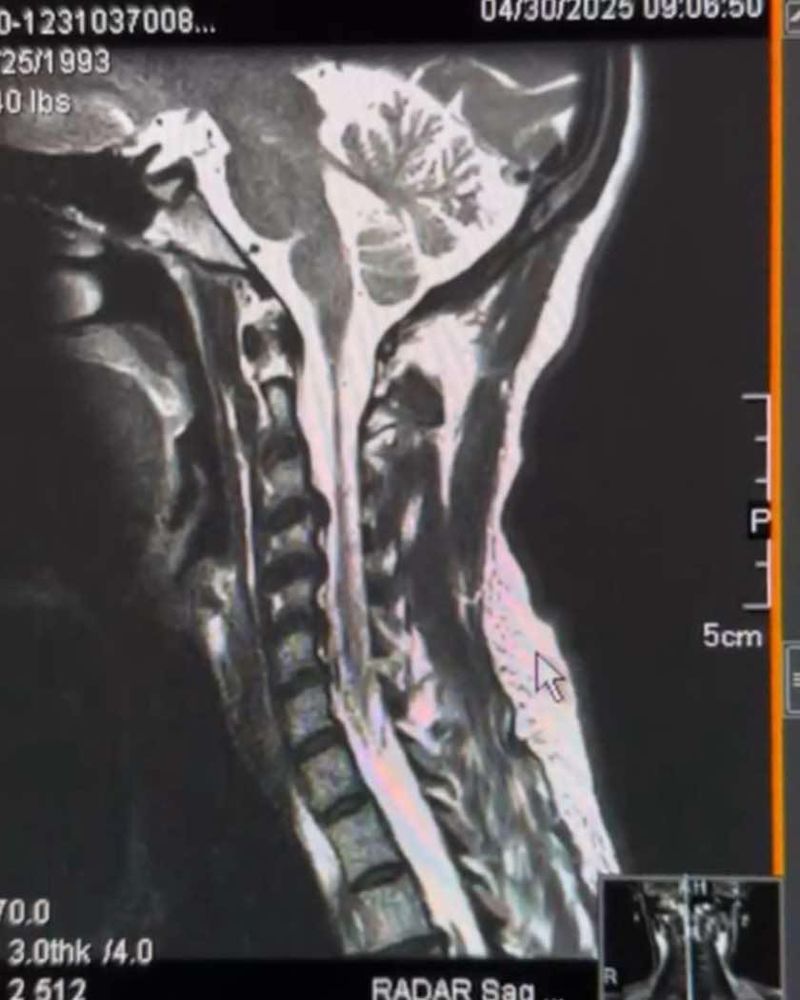

me seeing my spine: haha hell yes

my spine showing serious signs of damage: girl what the fuck

this post brought to you by: i have to have surgery on my spine. enjoy these vaporwave-esque photos of my neck